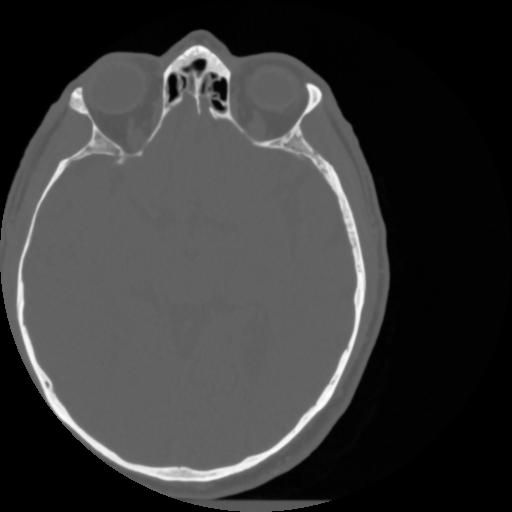

4 CEREBRO,,Vol,0.5,CEREBRO,,